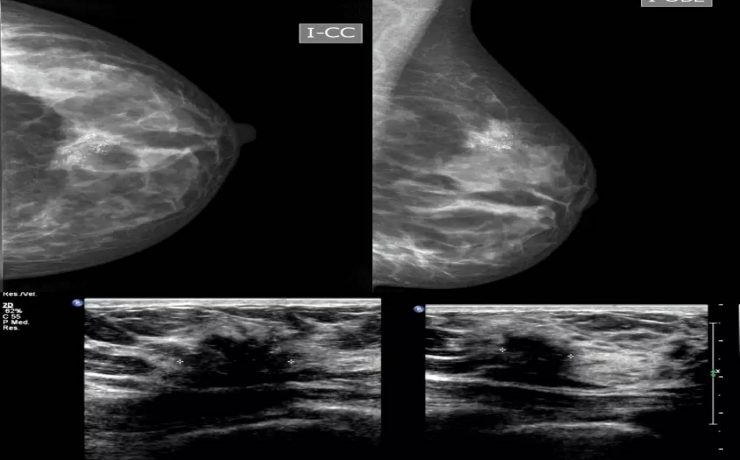

El síndrome de Rokitansky, es la anomalía más grave del tracto reproductivo femenino. Consiste en la ausencia congénita de vagina y útero ausente o rudimentario, como consecuencia de la falla en el desarrollo Mûlleriano de la vagina y el útero. Este síndrome fue descrito por Rokitansky en 1838. Es la